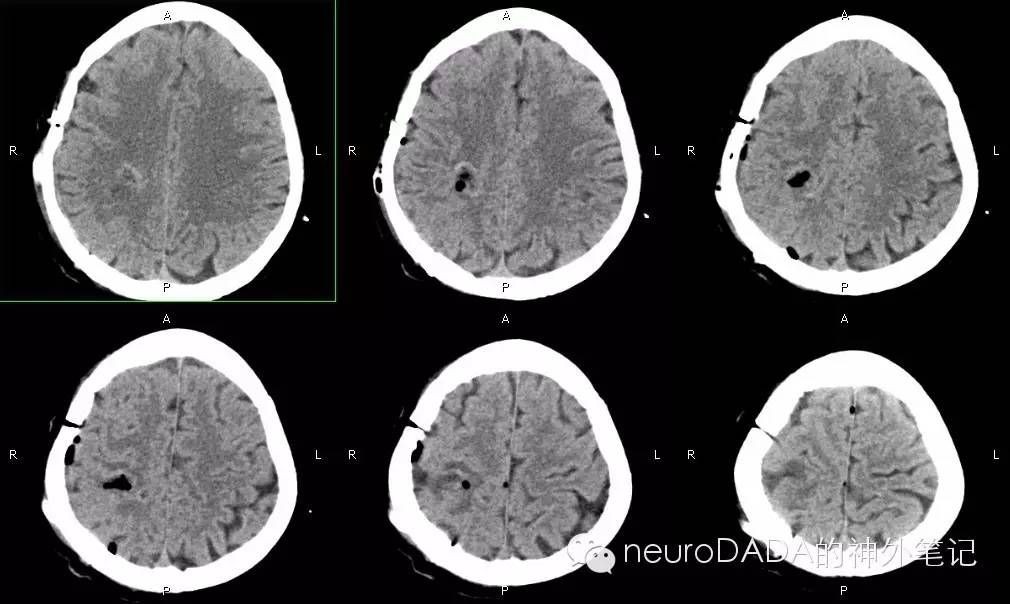

术后的CT复查,完全是经脑沟入路,未损伤皮层。病人无任何神经功能障碍。

两套方法不相吻合,选哪个。。。当时还是对自己的解剖定位没有信心,于是选择了方法一。。。果然,打开硬膜,深深的中央后沟和顶间沟就在骨窗的后上边缘了,还好骨窗做足了,至少看到了这脑沟,我也算送了口气。。。接下来的经脑沟入路海绵状血管瘤切除术就交给老板了。。。

回过头分析方法一失败的原因,可能主要在于病变上下位置定得太低了,而这是通过层面x层厚算出来的,这个方法的缺点就是,在我们的电子系统内似乎查询不到精确的层厚,同时由于每个病人头位摆放的不标准,似乎也难以找到确切的耳眦线层面(这个日后得请教一下我们医院的放射科)。尽管如此,我还是觉得结合两种方法来定位能提高准确性,也能不断锻炼我们的“see--Xray-”。